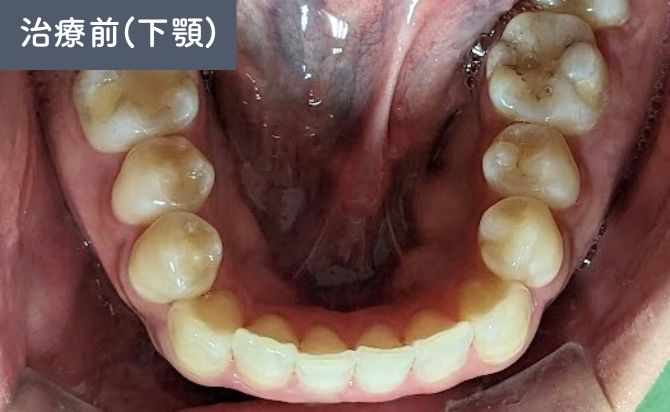

歯並びの変化(下)

上顎1番の前方位が確認され、口元の突出感に影響していました。また、上顎2番の舌側傾斜があり、歯列全体の並びにも不均衡がみられました。

さらに、下顎歯列弓が方形型であることから、上下のアーチ形態のバランスが整っておらず、前歯部の噛み合わせにも改善の余地があると判断しました。